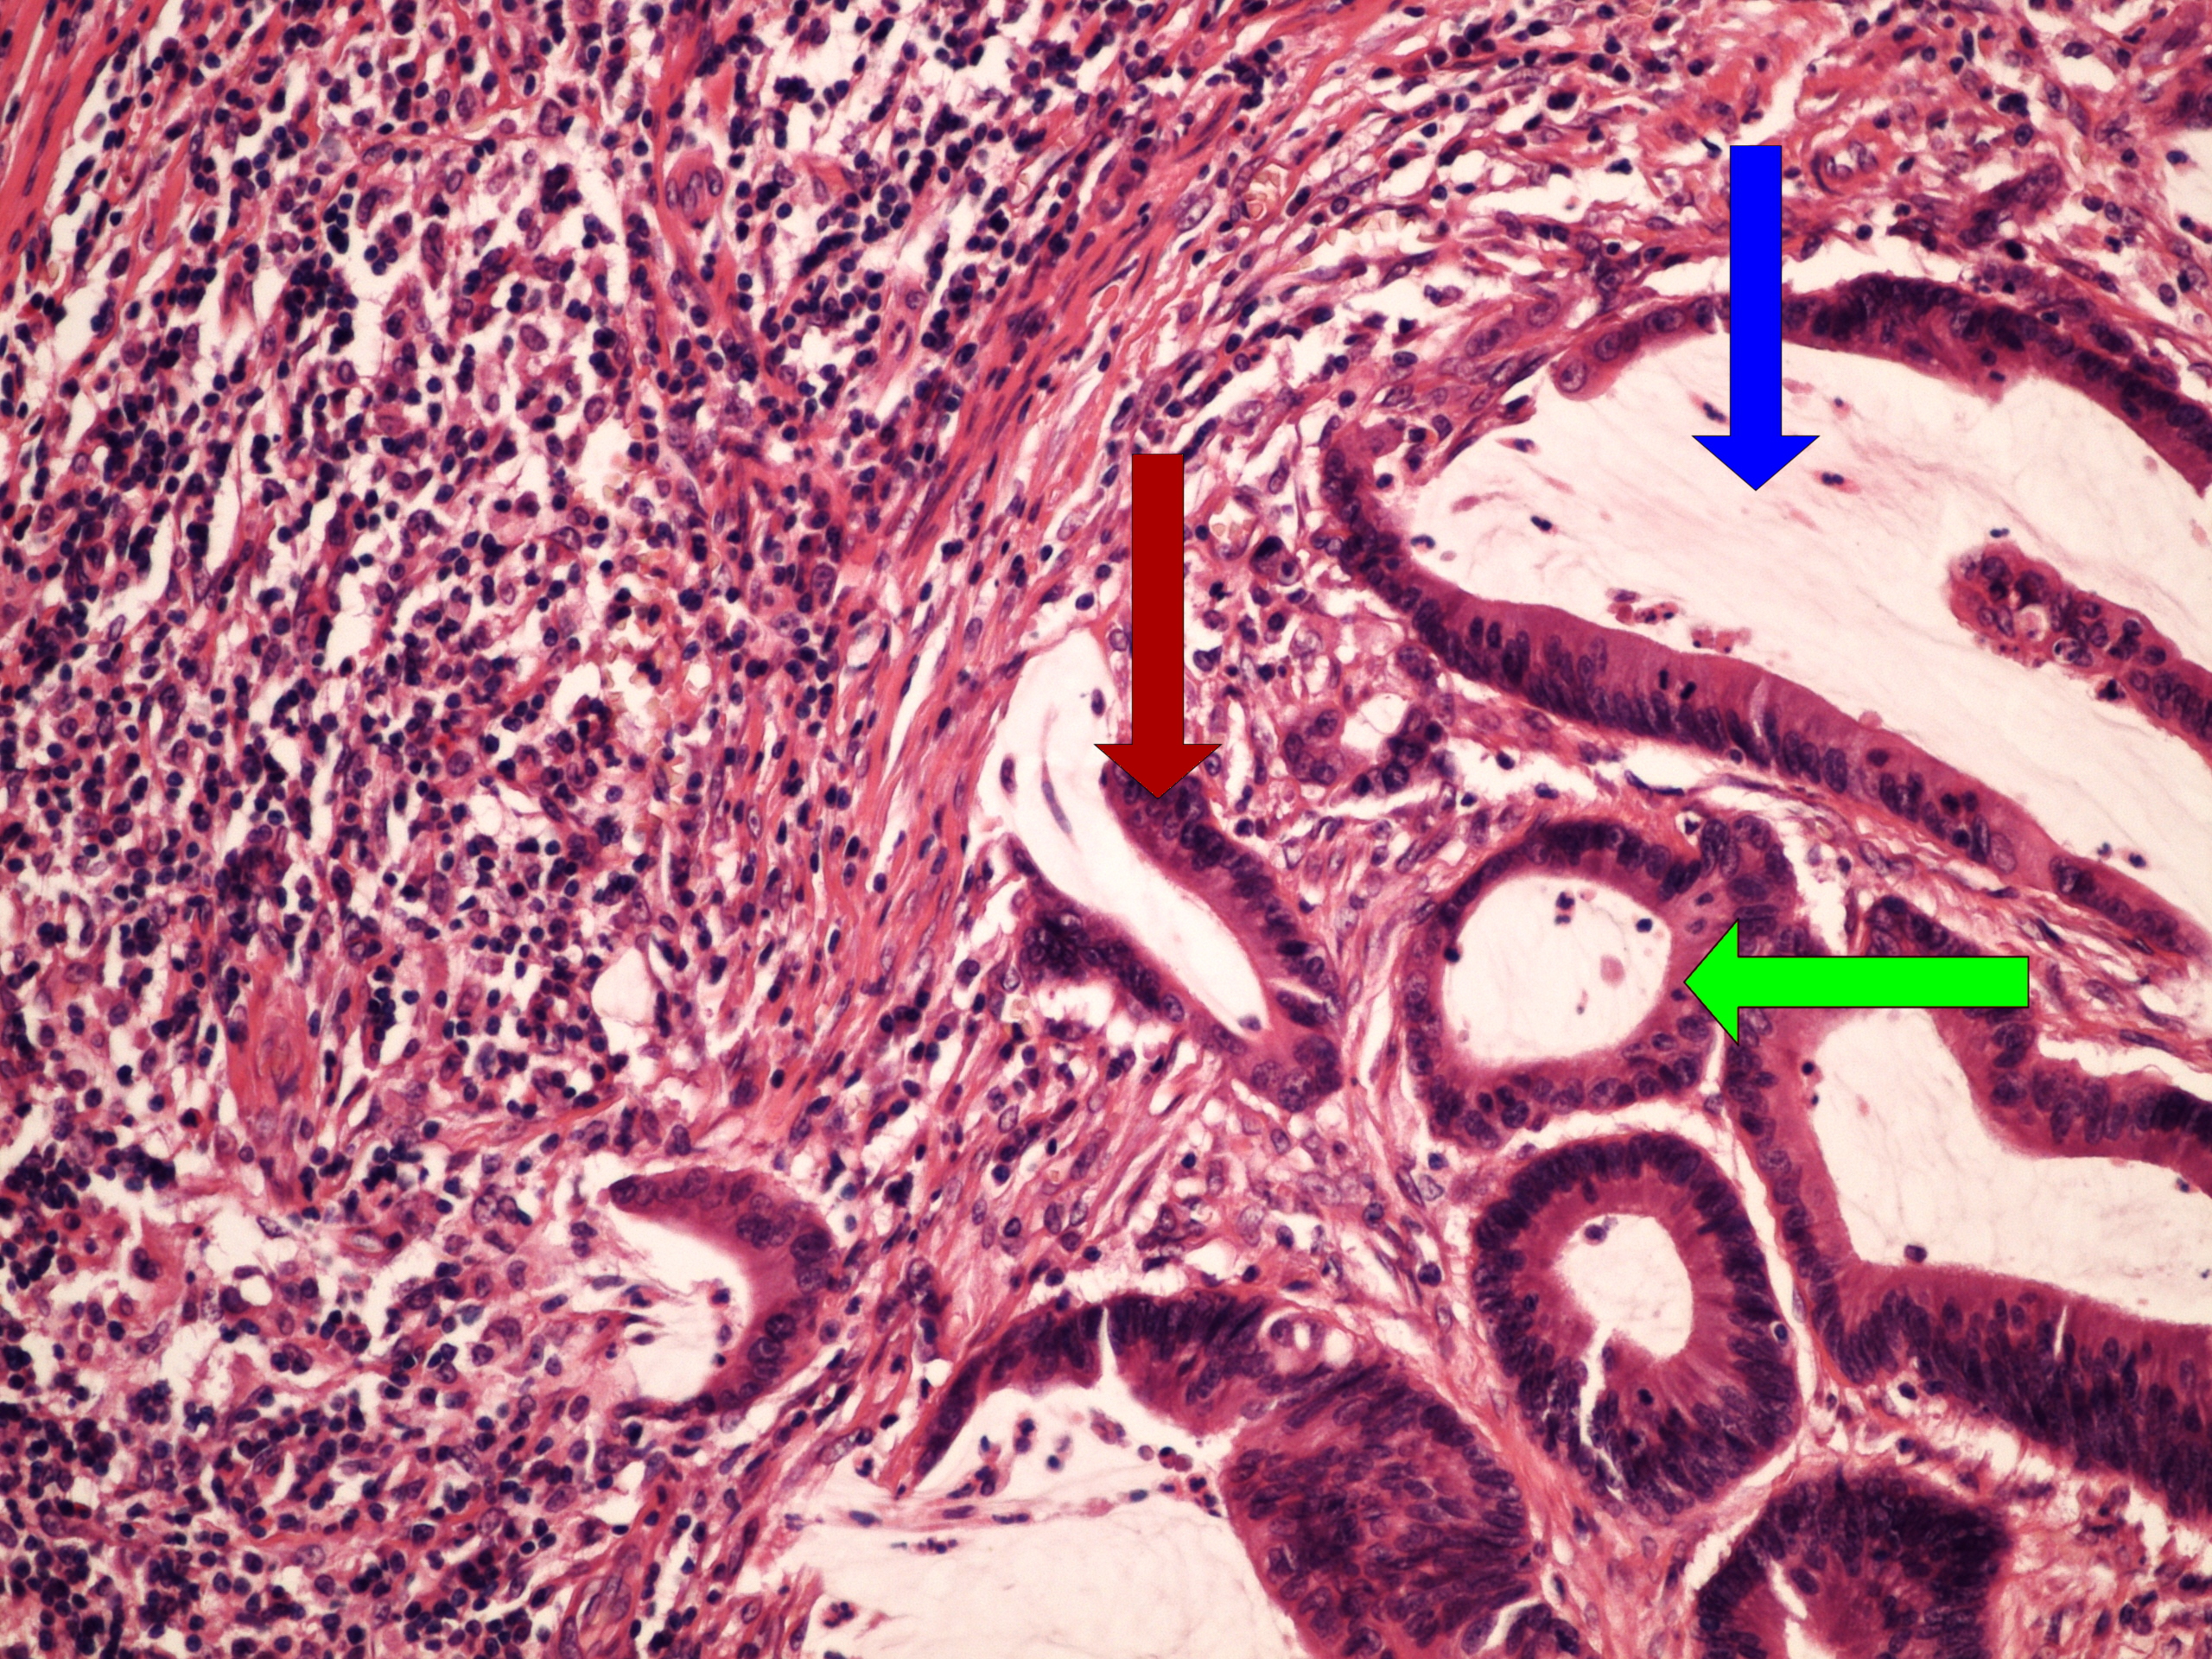

Preparát č.19 a č.20 - uroteliální papilokarcinom

Struktury

- papila

- stroma

- atypické urotelie